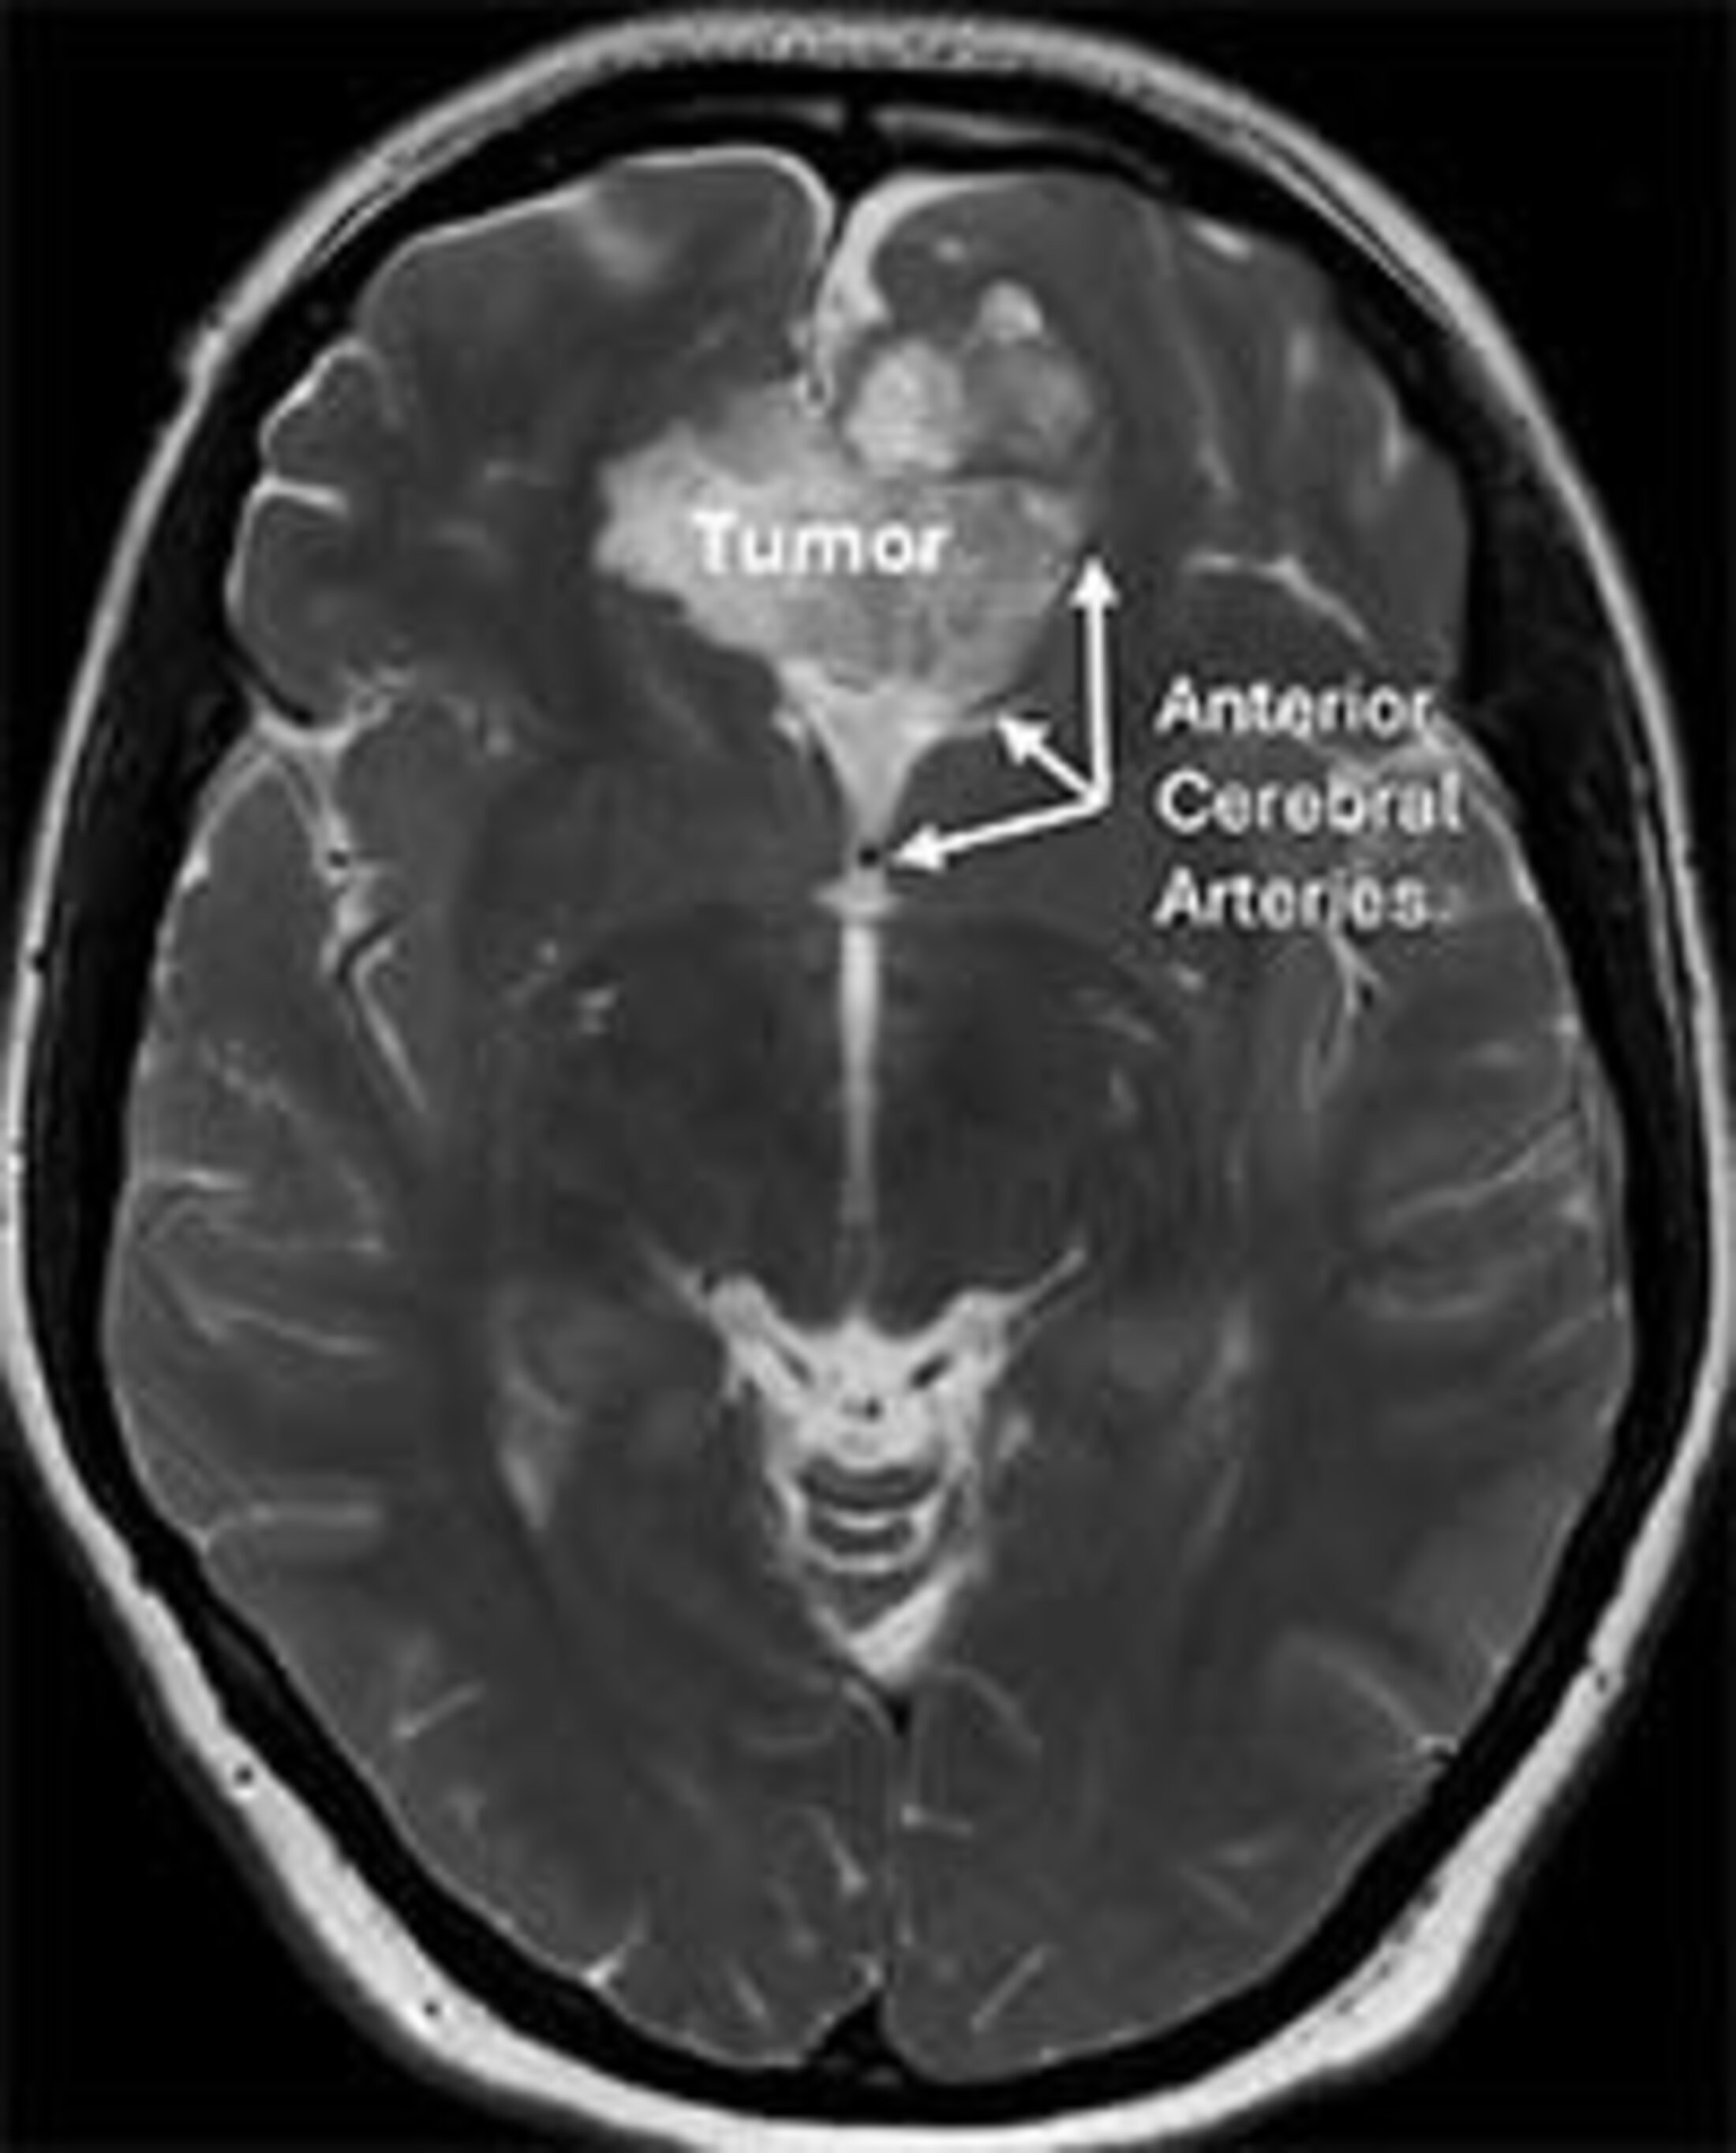

During the three-to-four-hour-long procedure, Martinez removed the dermoid cyst and some other smaller benign tumors called meningiomas.

“The way I did it was a craniotomy over the big vein on the brain and then dissecting in between the hemispheres to get down there. Sometimes, tumors get stuck to the blood vessels. Hers was a little stuck to the anterior cerebral arteries. Those arteries supply the area of the brain that helps you move your legs. So if I injured those arteries, then she would be paralyzed,” he said.

“But we were able to work under the microscope and peel it off the artery and remove it. The tricky thing is you always try to remove all of the cyst because if you leave some behind, it can grow back or its irritant contents can spill out and cause meningitis or seizures.”